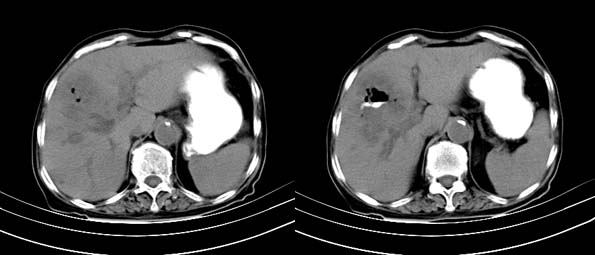

以下是引用bailaode在2008-6-12 22:10:00的发言:[br]资料中未提及患者有无急腹症体征,这个很重要。[br] ct表现:肝内境界模糊之低密度灶,内有含对比剂之液气平面.(提示肝内病灶与胃肠道沟通) [br] 1、根据“长城干红 ”所提供的资料“患者,女,74岁,黑便月余,消瘦,一般状况差,白细胞1万四千”,是否可认为是个慢性病程?那么我首先考虑:十二指肠结核,十二指肠--胆管瘘,继发胆道逆行感染肝脓肿形成。[br] 2、如有急腹症体征则考虑:十二指肠溃疡穿孔?十二指肠占位伴穿孔?

以下是引用拾荒者在2008-6-13 22:13:00的发言:[br]病灶与升结肠、肝脏及十二指肠关系密切,且结肠降段见造影剂影,支持结肠与十二指肠瘘形成,原因及原发病在哪不好定,不过,虽说有风险,但还是应该手术治疗,单纯抗感染估计不行。